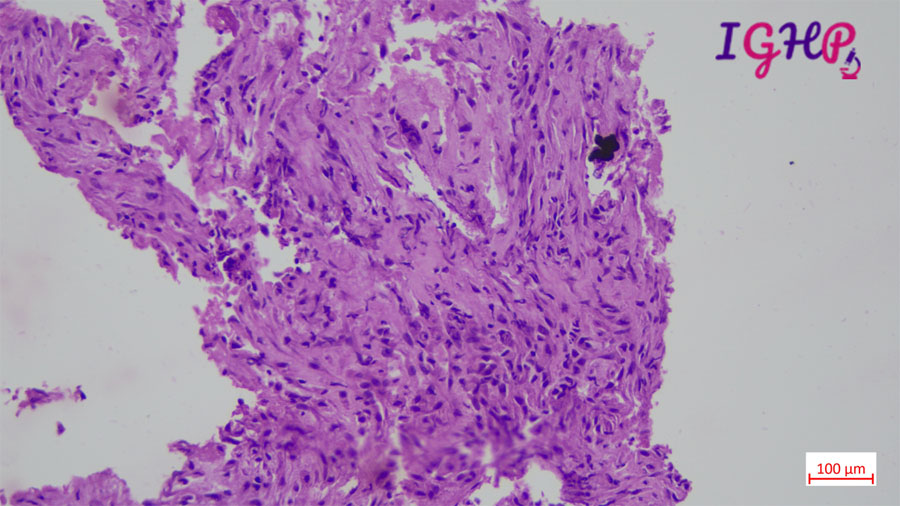

Histology-

Section from the pancreatic biopsy showed scanty large atypical cell in fibro collagenous stroma